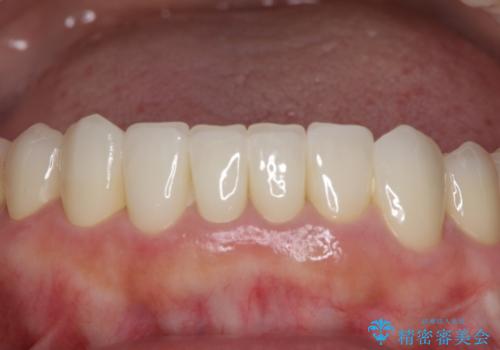

- 下顎の前歯に激痛を覚えて来院された患者様です。

取り急ぎ下顎前歯数歯の根管治療を、銀座しらゆり歯科医院長の林先生にお願いし、それ以外に気になっている、不自然な色調のクラウン、金属部分が見えてブラッシングがしにくいインプラント補綴、口元の突出感、出血のしやすい歯周ポケットなど、全てを解決するための治療を行うこととしました。

期間と費用はかかりましたが、気になっていた部分全てを改善でき、患者様には大変満足していただきました。